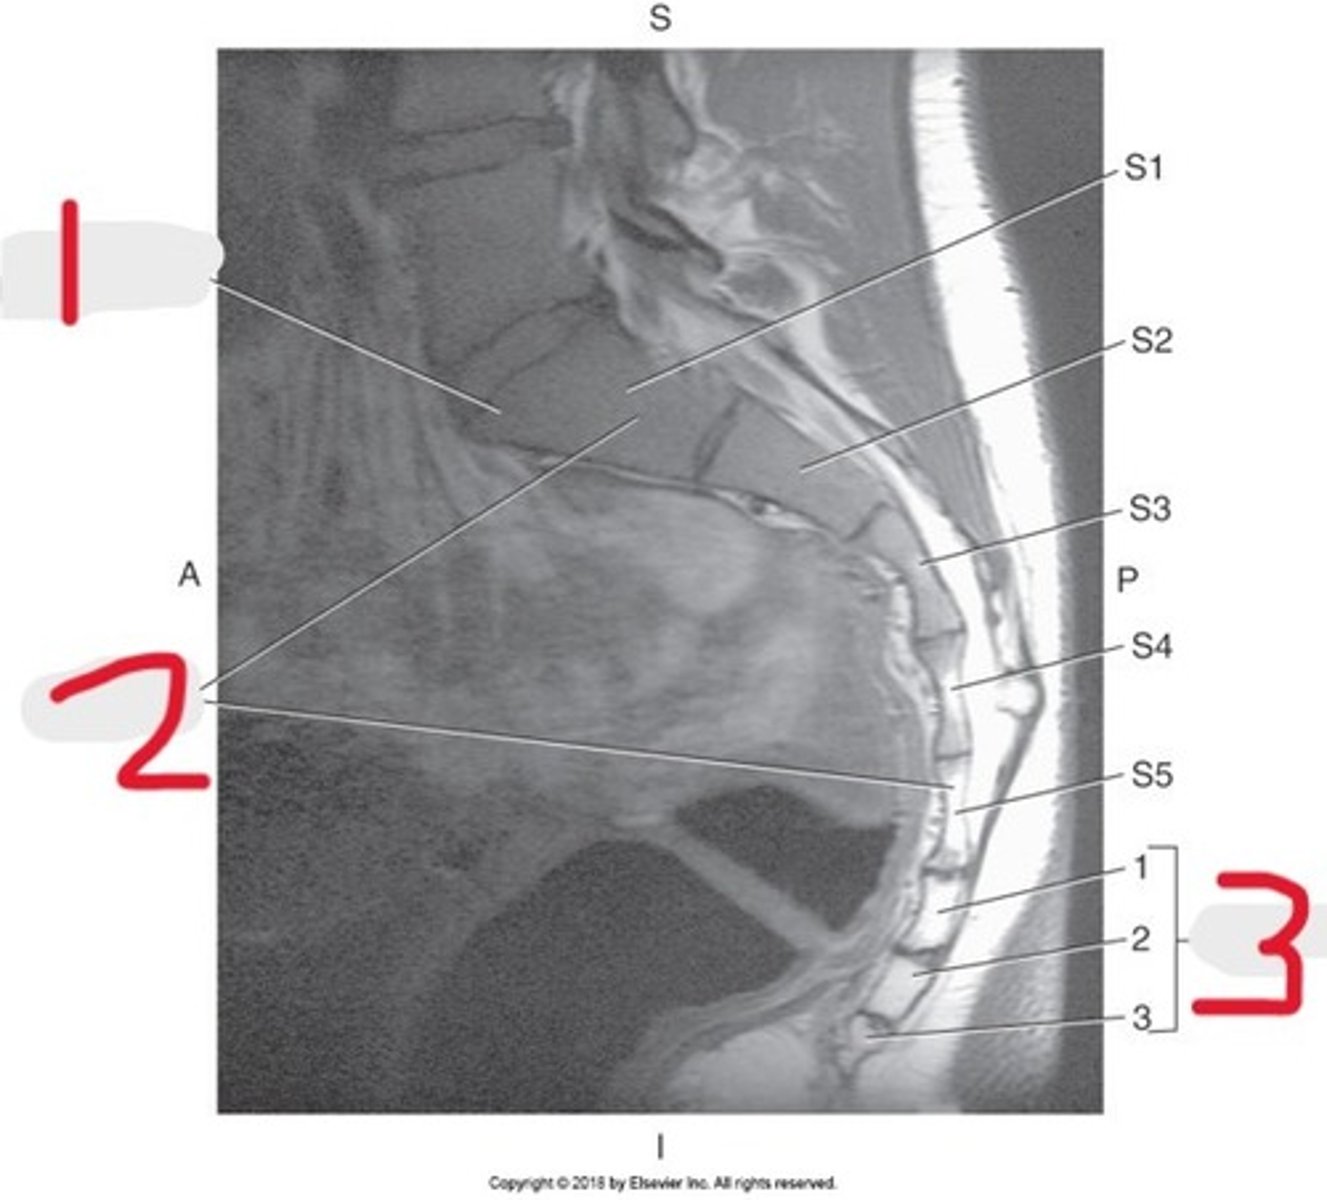

1) Conus medullaris

2) Cauda equina

3) Thecal sac

Name all numbered structures

1) L5

2) Sacrum

3) Conus medullaris

4) Cauda equina

5) Subarachnoid space with contrast

Name all numbered structures

1) Sacral promontory

2) Sacrum

3) Coccyx

Name all numbered structures

1) Sacrum

2) Conus medullaris

3) Cauda equina

Name all numbered structures